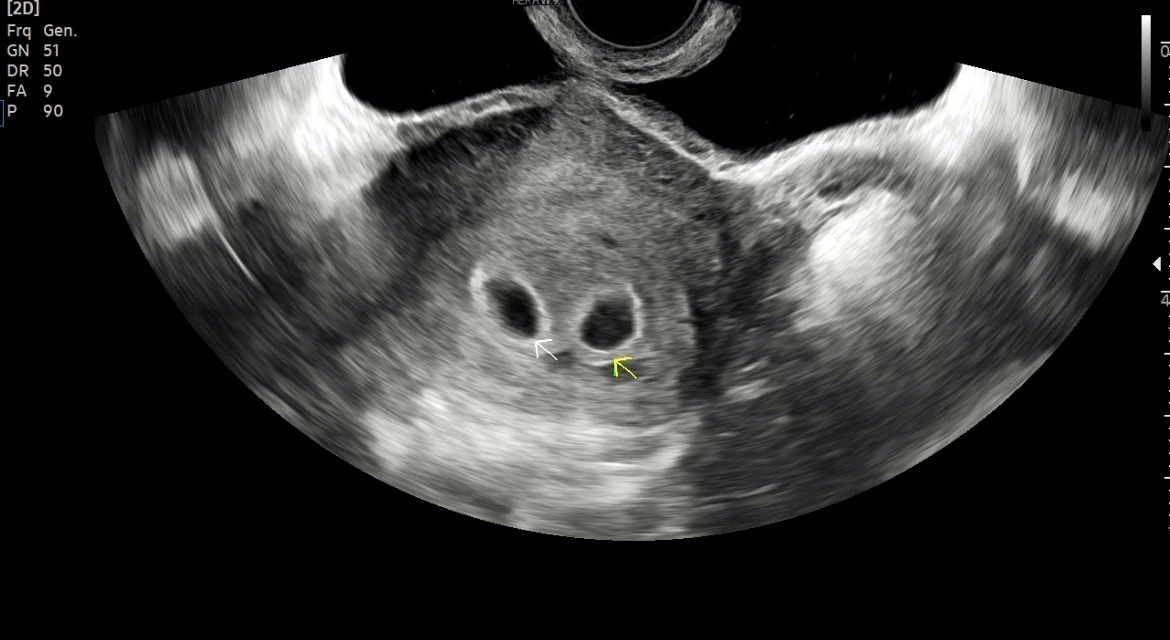

간호사님의 호명이 끝나고 우리 부부는 임신 이후 첫 진료를 받았다. 간단하게 담당 선생님과 인사를 하고 아내는 바로 초음파 검사 준비를 했다. 나는 1분가량 있다가 초음파 검사실로 들어갈 수 있다. 아내가 초음파 검사를 위한 준비가 있기 때문에 그 시간이 약 1분가량? 1분이 조금 안되었던 것 같기도 하다. 아내는 검사를 받는 전동 침대 같은 곳에 누워있었고 의사 선생님이 의료 기기에 젤을 묻히고 자궁 쪽을 검사하기 시작했다.

지난번에 들었던 아기집을 다시 볼 수 있었다. 아기집이라는 게 어떻게 아가로 변하는 건지 정말 신기했다. (앞으로 그 과정은 차근차근 글로 담아보겠다.)

KakaoTalk_Photo_2023-10-28-23-18-12 002.jpeg 뚜렷하게 보이는 아기집, 이때 우리의 궁금증은 일란성인지 이란성인지였다.

아직 모른단다. 언제쯤 알지도 모를 수 있단다. 우선은 아기집이 잘 보이고 건강하게 커야 하기 때문에 일산성이냐 이란성이냐의 문제는 나중으로 미뤄버렸다. 다시 한번 시험관이 아닌 자연 임신으로 쌍둥이 임신을 하게 된 것을 축하한다는 의사 선생님의 인사와 함께 본격적인 산부인과의 두 번째 일정을 마무리했다. 점차 커갈 우리 쌍둥이들을 기대하며 우리는 다음번 진료를 예약하러 갔다.